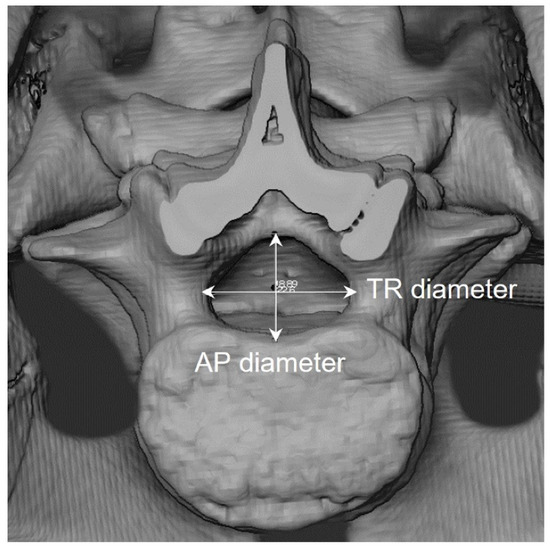

Figure 7.

Antero-posterior (AP) and transverse (TR) vertebral neural canal (VNC) diameters taken on virtual surfaces reconstructed from CT scans.

2.3.2. Vertebral Neural Canal Measurements (VNC)

Antero-posterior (AP) and transverse (TR) diameters of vertebrae thoracic 10 to lumbar 5 were collected following definitions by Watts [55,56]. The data were measured on the virtually reconstructed surfaces in the four countries that provided CT images (France, The Netherlands, Taiwan, the United States) (Figure 7) and collected directly on the dry vertebrae in the Colombian sample.